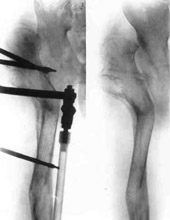

Congenital dislocation of right hip.

Schanz-Ilisarov's operation with elongation of hip.Schanz-Ilisarov's operation with elongation of hip.

Schanz-Ilisarov's operation with elongation of hip.